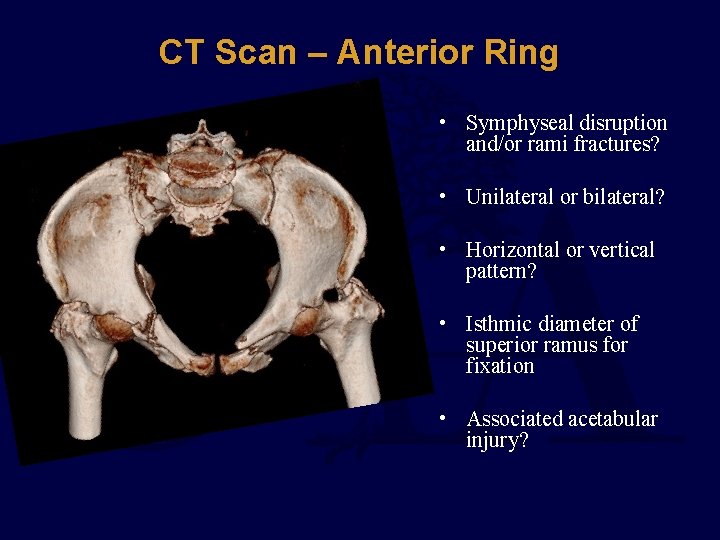

CT Scan – Anterior Ring • Symphyseal disruption and/or rami fractures? • Unilateral or bilateral? • Horizontal or vertical pattern? • Isthmic diameter of superior ramus for fixation • Associated acetabular injury?